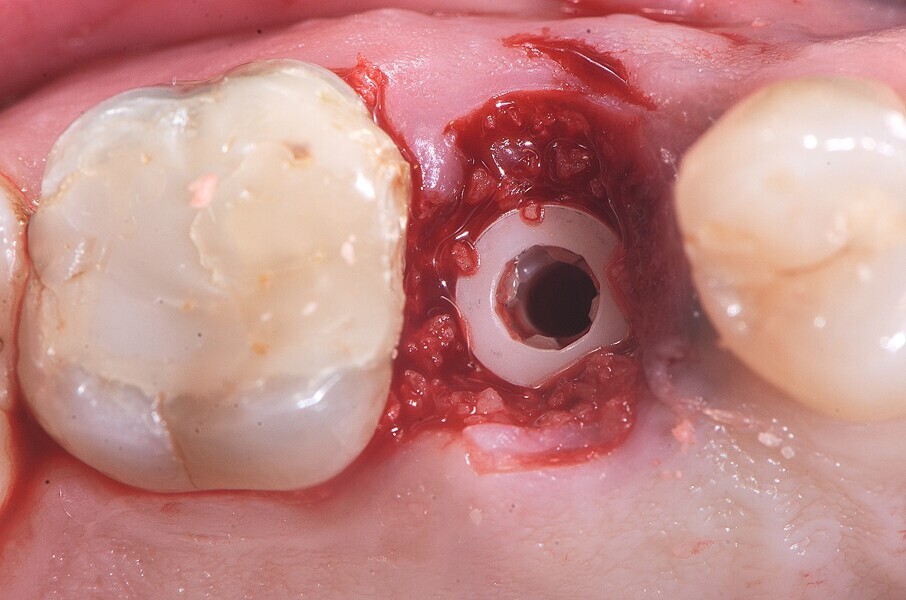

Fig. 17: Pose de l’implant deux pièces en céramique au niveau tissulaire.

Fig. 18 : Pose de l’implant deux pièces en céramique au niveau tissulaire.

Fig. 19 : Pose de l’implant deux pièces en céramique au niveau tissulaire.

La pose immédiate d’un implant deux pièces en céramique au niveau tissulaire a été accomplie tout en préservant l’alvéole (allogreffe constituée d’un substitut osseux et protection par une membrane de collagène résorbable). La mise en charge n’a pas été réalisée à ce stade (Figs. 12–24)